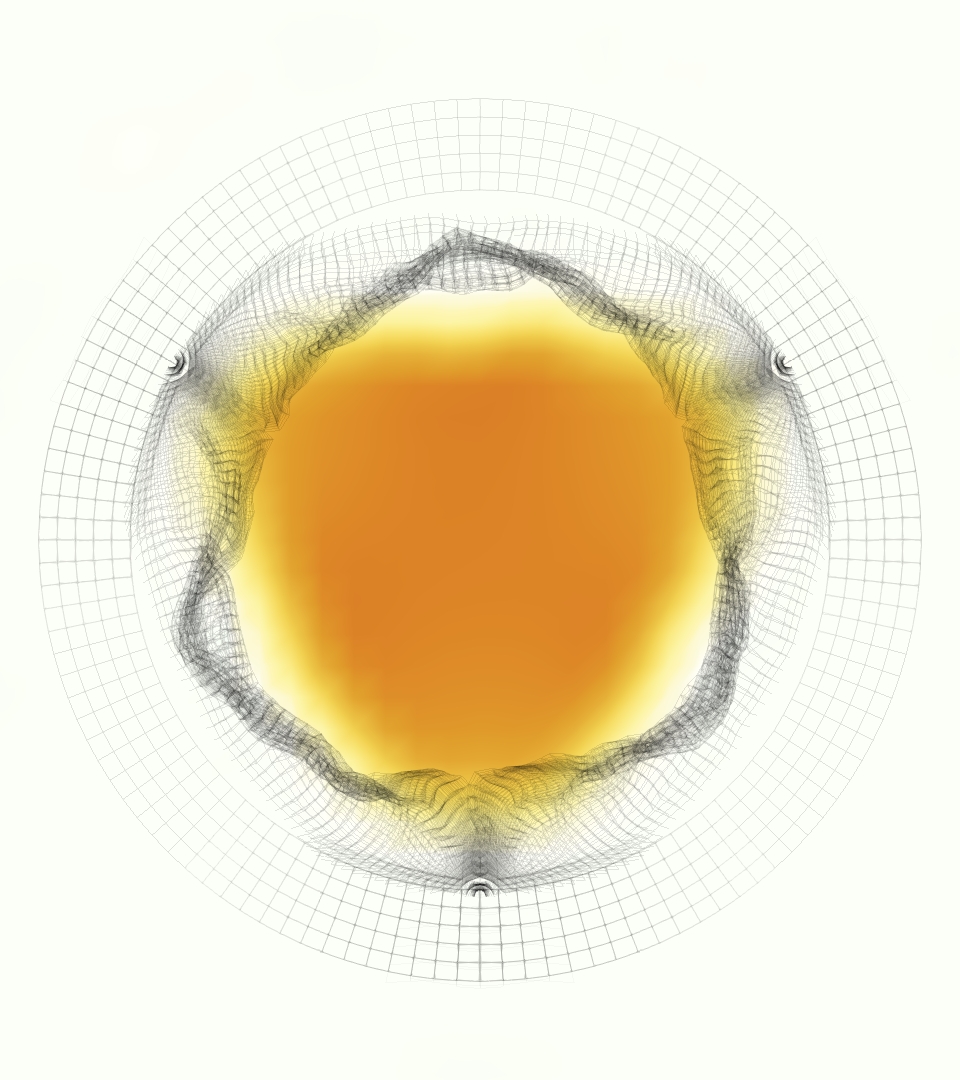

The gross morphology of the model valve that emerged from this process is shown in Figure 4. The free edge was 2.87 cm, corresponding to 3.3 cm in the predicted loaded configuration. After the pinching the leaflets together at the commissures, this left approximately 2.1 cm of free edge rest length per leaflet free to move independently of the other leaflets, within measurement error of ±0.1 cm from the free edge length of 2.2 cm measured on the prostheses. The leaflet rest height was 0.94 cm corresponding to a predicted loaded height of 1.44 cm. The measured leaflet height of 1.3 cm is nearly the predicted loaded height of 1.44 cm, which may be because the leaflets are so compliant in the radial direction, that pulling them flat to measure them achieved substantial stretches. The fiber orientation of the model runs from commissure to commissure and qualitatively matches experimental observations [38], though direct quantitative comparison is beyond the scope of this work. One minor limitation is that we do not add bending rigidity to the leaflets, beyond what emerges from the thickening process described above, and thus may not accurately capture leaflet flutter or other similar behaviors. Based on the thickness of mm, we estimated the mean tangent modulus at the predicted loaded stretches as dynes/cm2 circumferentially and dynes/cm2 radially. The prosthetic valve tissue is fixed in glutaraldehyde, and literature values for the fully-recruited circumferential tangent modulus of fixed porcine aortic valve tissue vary widely. Based on the experimental measurements of Billiar and Sacks and their constitutive law for valves fixed under 4 mmHg of pressure, we evaluated their constitutive law at the relevant stretches and and estimated the circumferential tangent modulus to be dynes/cm2 [6]. Rousseau et al. reported moduli ranging from to dynes/cm2, depending on the applied preload during fixation [36]. Sung et al. reported moduli ranging from to dynes/cm2, depending on fixation pressure [43]. Thus our estimated tangent modulus falls within the range of existing studies, so we considered our resultant modulus in good agreement given the complexity of the steps involved, phenomenological nature of the constitutive law and uncertainties in experiments. We do not have access to the precise material properties of the prosthetic valve, and further, the only literature we could find on the material properties of a similar prostheses reported the tangent modulus at one particular loading, which did not appear to be at a relevant stretch for comparisons with our model [19]. Thus, our model has material properties in a reasonable range for a fixed aortic valve prostheses (placed in the pulmonary position in our simulations), but it does not directly model the material properties of the prostheses.

We constructed the model vessel for FSI simulations from data from the MRI scans (Figure 4). The signal magnitude of 3D printed model material is distinct from the signal of the fluid in the scans, and we applied a thresholding operation to generate a three-dimensional model of the printed vessel surface. Using the MRI data ensured that the MRI and simulation coordinates were consistent in space and there were no alignment or registration errors. While using the files that generated the 3D printed model would have offered more spatial fidelity, the potential error in flow fields due to any mis-registration would have likely been much more substantial. Using Meshmixer (San Rafael, CA), we smoothed the mesh to remove stair-step effects and removed artifacts from the valve scaffold. We then remeshed to the desired edge length of 0.25 mm and extruded the model 0.25 mm and 0.5 mm to create a three-layer structure. As in the valve, this serves to eliminate the “grid aligned artifact” that can occur with pressure differences across thin membranes in the IB method [16]. Flow extenders of length 1 cm were added to the vessel at the inlet and both outlets to ensure that the normal to the vessel was aligned with the normal of the fluid box at the inlets and outlets. In FSI simulations, the vessel was held in place using target points, stiff springs of zero rest length that connect the current position of each model node to its desired position (Section 3.3). Additional linear springs are placed on each edge in the triangulated model. These springs are not meant to model a particular material and only serve to keep the vessel rigid and stationary throughout the simulation.